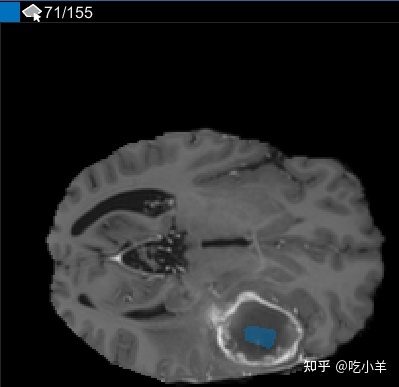

使用插值后,检查单个切片以查看插值是否创建了令人满意的 ROI。请注意,切片 71 上的 ROI 并未填充您要分割的整个对象。您可以使用手动调节ROI笔刷工具。或者,您可以使用“自动化”选项卡上的工具之一。例如,您可以使用Active Contours在未填充肿瘤全尺寸的切片上增加 ROI。您还可以使用添加算法来指定您自己的算法来对 ROI 进行操作。